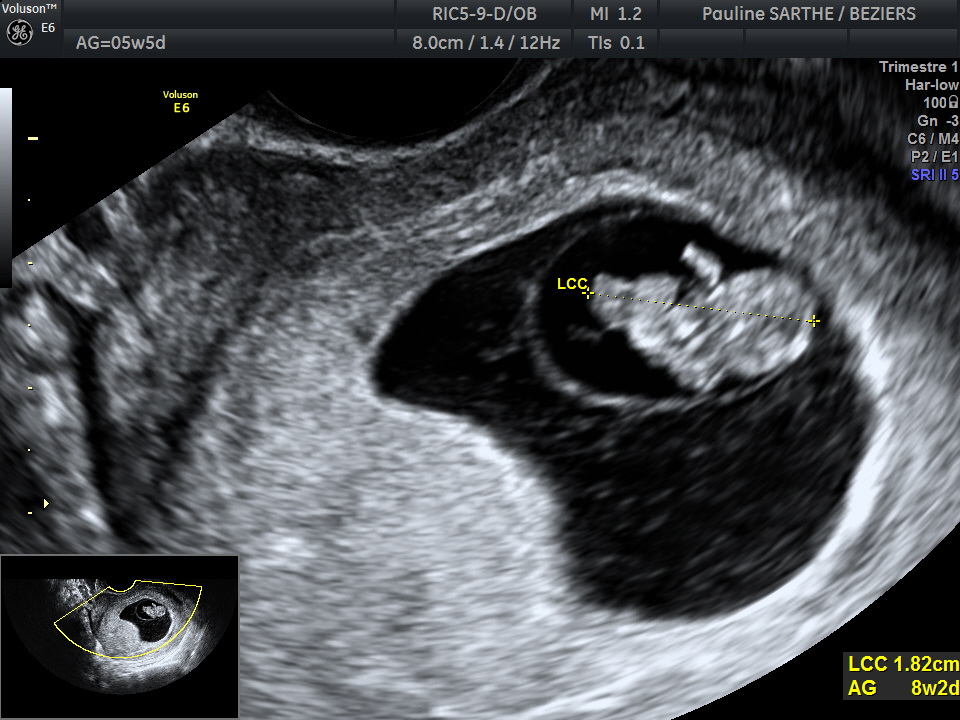

- l'échographie de datation permet de savoir très tôt si la grossesse est bien plaçée dans l'utérus et se déroule bien, s'il s'agit d'une grossesse simple ou géméllaire.

Elle n'est ni obligatoire ni systématique mais peut-être demandée entre 4,5 et 11 semaines d'aménorrhées si:

- vous avez des cycles irréguliers ne permettant pas de dater la grossesse avec précision

- vous avez des douleurs ou un saignement

- vous avez des antécédents pathologiques (fausse couche, grossesse extra-utérine)

- enfin en cas de Procréation Médicalement Assistée avec risque de grossesse gémellaire ou de grossesse multiple

-en cas de demande d'interruption de grossesse (prise en charge à 100% par la sécurité Sociale) REIVOC